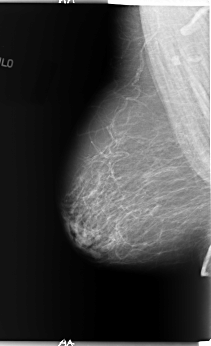

B_3089_1.LEFT_MLO

FILE: B_3089_1.LEFT_CC.OVERLAY

TOTAL_ABNORMALITIES 1

ABNORMALITY 1

LESION_TYPE MASS SHAPE ROUND MARGINS CIRCUMSCRIBED

ASSESSMENT 4

SUBTLETY 4

PATHOLOGY MALIGNANT

TOTAL_OUTLINES 1

BOUNDARY